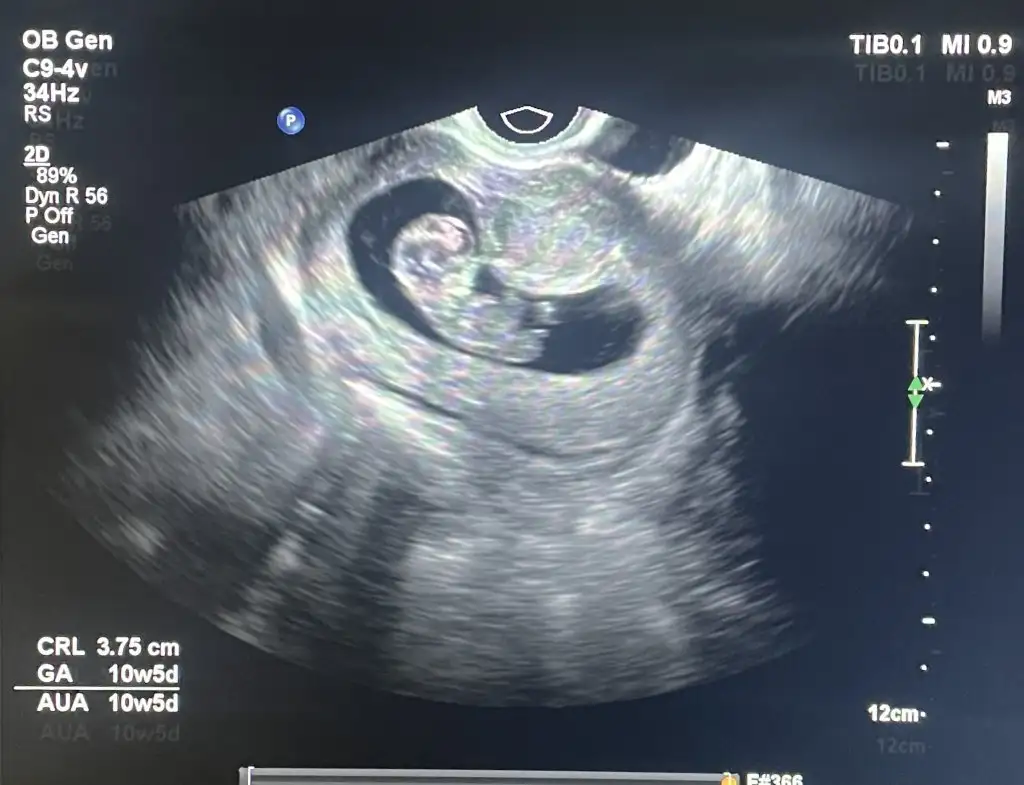

Kızlar merhabalar

Ağlamaktan bitmiş durumdayım

Muayene olduk karından bebeği de keseyi de göremedi

Vajinal baktı kese basık duruyo bebek büyümüş elektrik sinyali var ama kalp atışı yok dedi

10 gün önce kalbini duymuştuk o zamandan sonra 9 günde 5 gün büyümüş dedi bebek 7 cm miş

Kese bebeğe göre küçük duruyo

Cumartesi ye kadar bekleyelim duruma göre bakalım dedi

Geçen geldiğinizde de şans eseri kalbini duyduk kesenin şeklini beğenmemiştim ama size söylemek istemedim dedi

Eğer kalbini duymamış olsaydık haftaya gelin kalbini duyarız diye daha umutlu konuşabilirdim dedi ama şuan yüzde elli yüzde elli ihtimal dedi her ikisine de hazır olun dedi

Var mı benzer durum yaşayan veya düzelen

Ultrason görüntüsünü de ekliyorum anlayan olursa belki

Normalde 7+5 bugün ama ultrasona göre bebek 6+5 dedi

Ben tükenmiş hissediyorum bu benim 5.gebeliğim ve çok çok zor olan Bi gebelik

Öncesinde benzer durumlarda 4 kürtajm olmuştu

Sonuç aynı olmasın nolur Allahm 😔